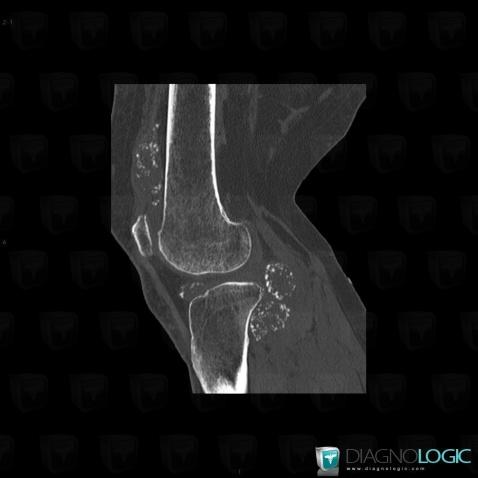

Ostéochondromatose synoviale, Fémur -inférieur, Tibia -supérieur, Scanner

Voici les informations spécifiques à l'image clé ci dessus:

- Diagnostic Ostéochondromatose synoviale, Localisation(s) Fémur - 1/3 inférieur, comportant les gammes Ostéolyse corticale, Erosion corticaleTibia - 1/3 supérieur, comportant les gammes Ostéolyse corticale, Erosion corticaleAutres parties molles/nerfs - Genou, comportant les gammes Calcifications des parties molles, Masse des parties molles avec ostéolyse, Masse calcifiée des parties molles, Masse des parties molles juxta articulaires